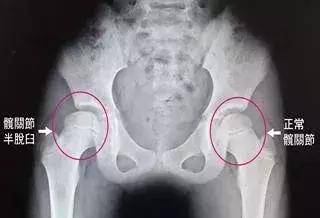

6个月以上的宝宝,股骨头骨化中心已经出现,不能做超声检查,这时就需要X光片检查发挥作用了。下图所示就是髋关节脱位宝宝的X光片,各位宝妈可以很明显得看出两侧髋关节发育得不对称,一旦发现这种情况,宝妈就需要带宝宝到专业的小儿骨科做进一步治疗了。